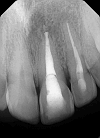

This case report highlights the successful healing of a large periapical lesion through non-surgical root canal retreatment. A 29-year-old male patient presented with a significant radiolucency associated with teeth #21 and #22, initially treated non-surgically. Despite the lesion's size, the treatment, which included thorough canal disinfection and obturation, led to substantial healing. A follow-up cone-beam computed tomography (CBCT) scan after one year confirmed the buccal cortical bone reformation and improvement in the incisive canal area except for the apical region of #21. Subsequently, root canal retreatment was performed for #21. Complete healing was achieved after two years, demonstrating that even extensive periapical lesions can be effectively treated with non-surgical endodontic retreatment, avoiding invasive surgical intervention.